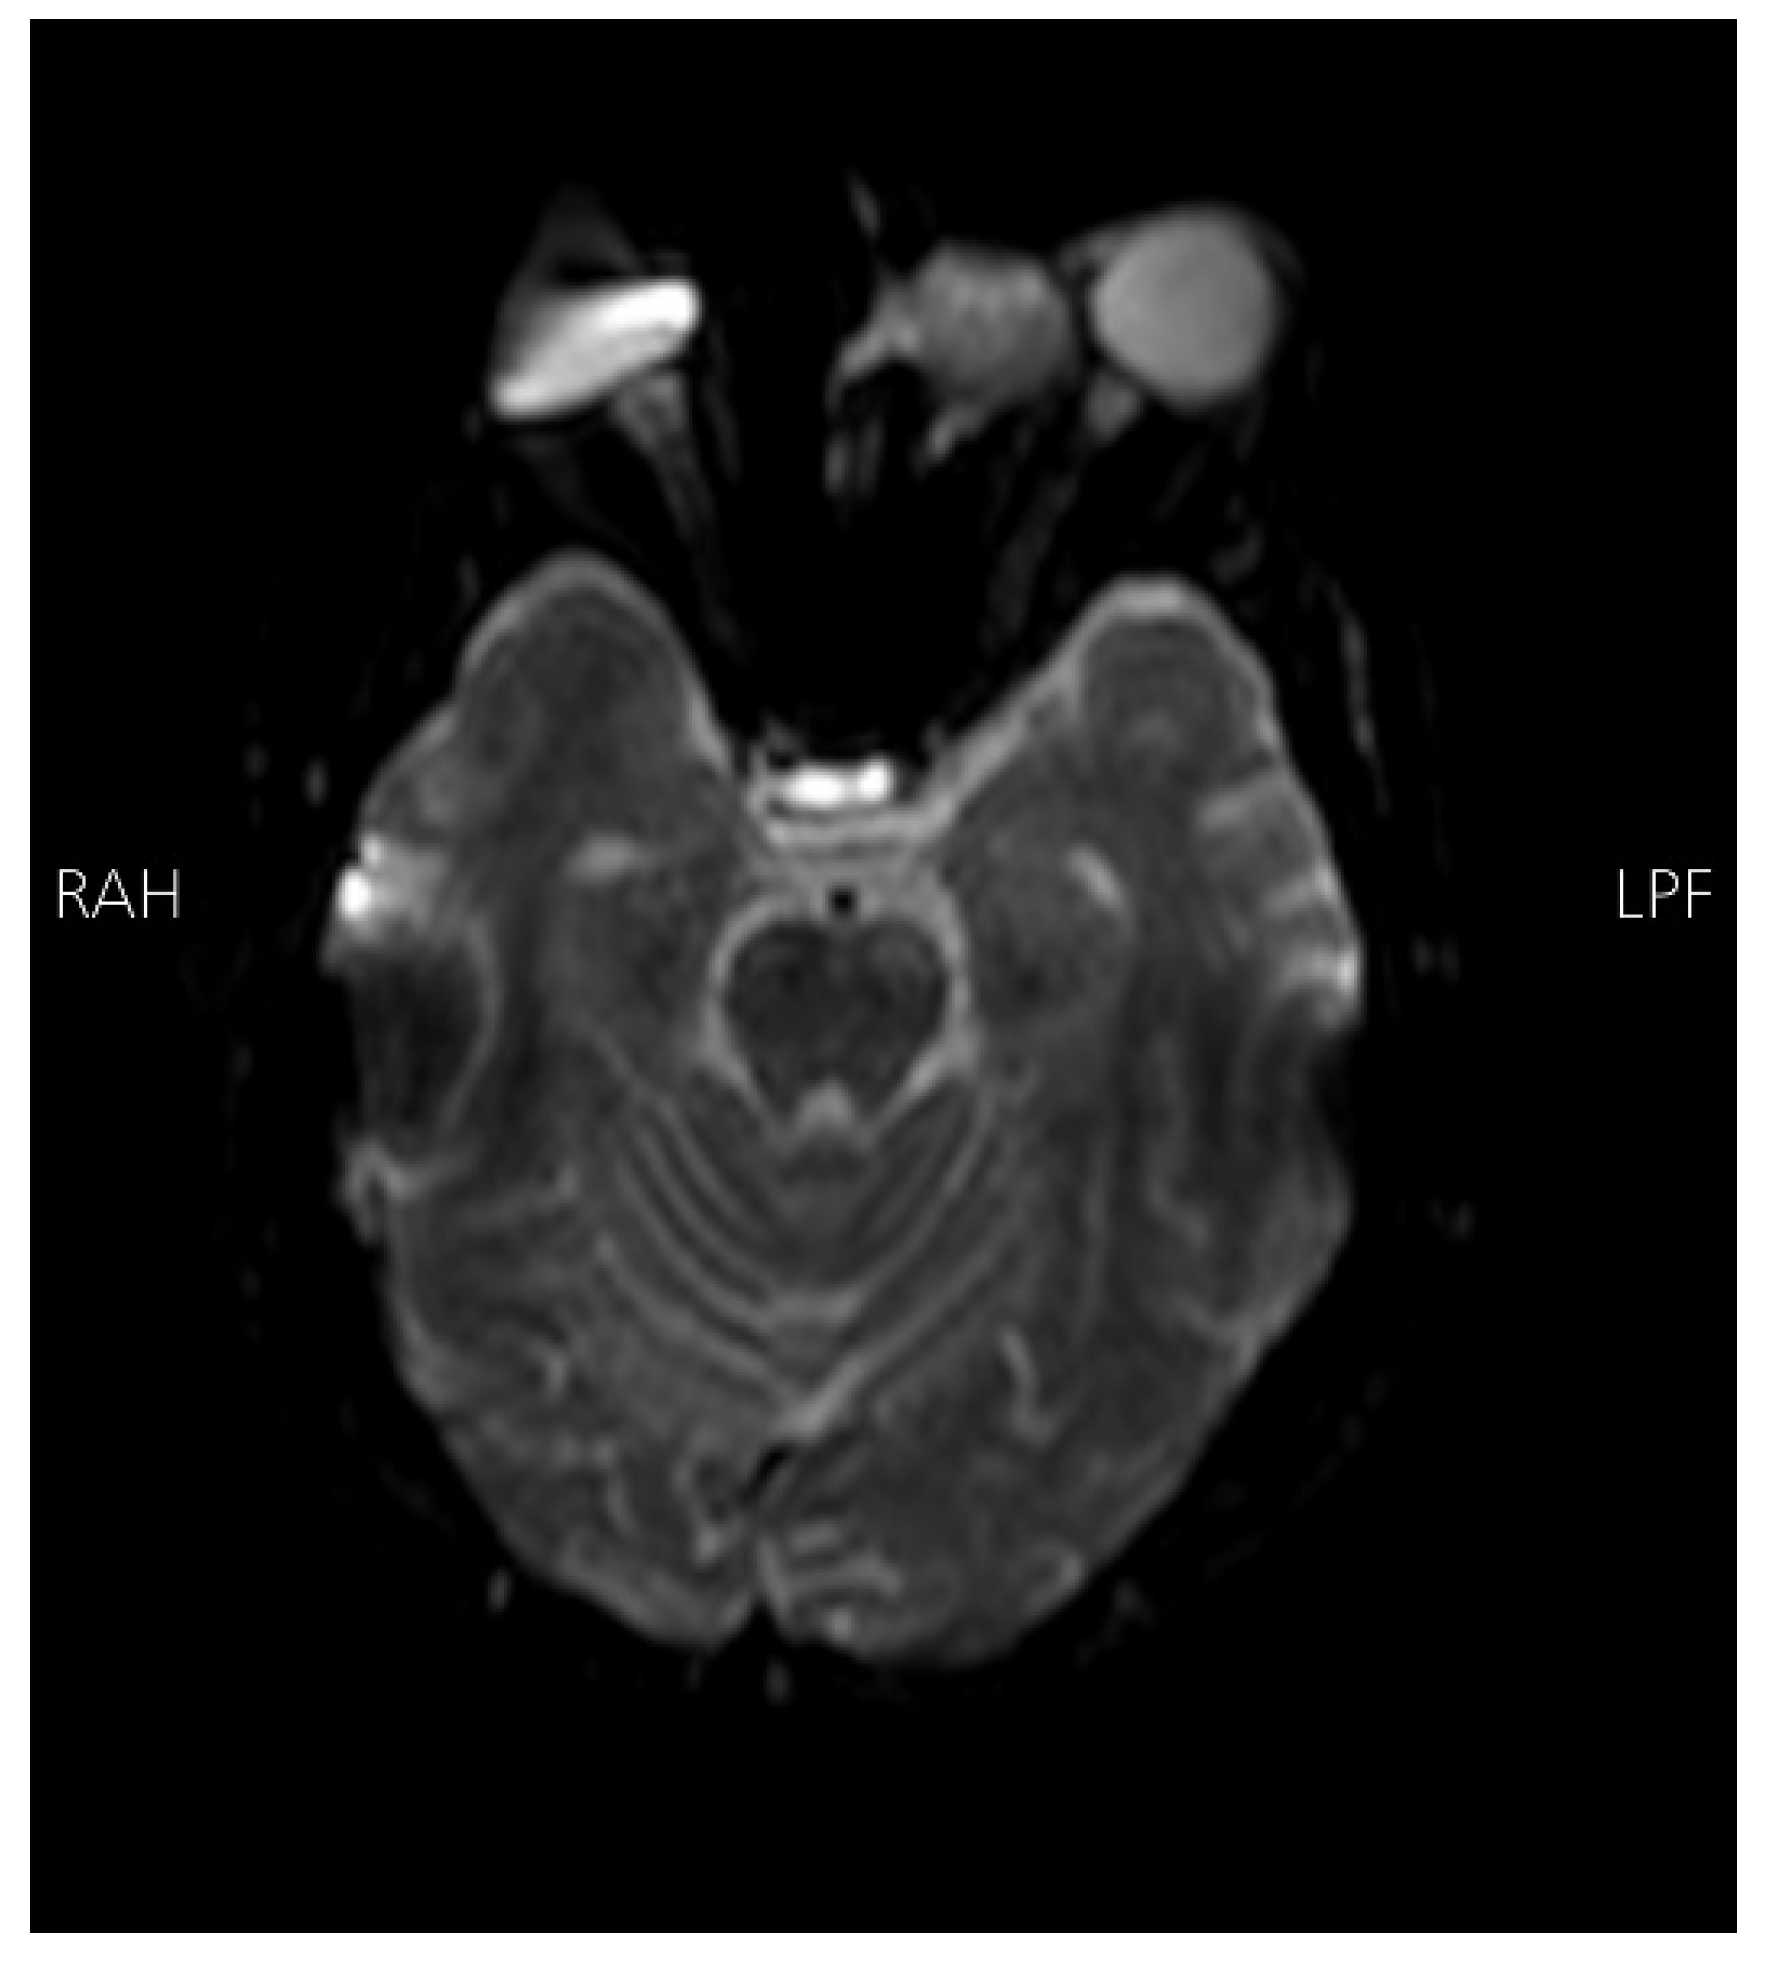

Radiological findings from high-resolution computed tomography (CT) (Figure 1) revealed bilateral basal ganglia hypodense areas suggestive of chronic ischemia and a more lateral hypodense area toward the left basal ganglia indicative of subacute ischemia. A coronal cut showed an iso-dense expansible soft tissue lesion with internal foci of calcifications centered in the anterior aspect of the left ethmoid sinus with protrusion to the left orbital conus, pushing the medial rectus muscle laterally with complete obliteration of the left frontal sinus. Brain magnetic resonance imaging with Fluid-attenuated inversion recovery sequence (MRI FLAIR) (Figure 2) showed an abnormal hyperintense signal in the left cavernous sinus and a left ethmoidal sinus synovial tumor.

Figure 1. High-resolution CT scan with an axial cut (Left side) showing a bilateral basal ganglia hypodense area suggestive of chronic ischemia and a nearby hypodense area at the left basal ganglia indicative of subacute ischemia (A). A coronal cut (right side) shows an iso-dense expansible soft tissue lesion with internal foci of calcifications centered in the anterior aspect of the left ethmoid sinus with protrusion to the left orbital conus pushing the medial rectus muscle laterally with complete obliteration of the left frontal sinus.